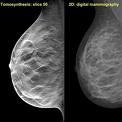

August 6, 2009 - The use of digital breast tomosynthesis and full-field digital mammography (FFDM) combined may be associated with a substantial decrease in recall rate, according to a study performed at UPMC in Pittsburgh, Penn., published in the American Roentgen Ray Society.

An estimated 10 percent of women in the United States are recalled for a second mammogram after an abnormality is detected on the first one. Some researchers believe that digital breast tomosynthesis depicts the breast tissue in a way which may allow radiologists to identify some tumors which could be missed with standard two-dimensional mammography.

In the study, 125 patients were evaluated using a combined method of digital breast tomosynthesis and standard digital mammography. The use of digital breast tomosynthesis and FFDM was associated with a 30 percent reduction in recall rate for cancer-free examinations that would have led to recall if FFDM had been used alone, reported Jules H. Sumkin, M.D., one of the authors of the study.